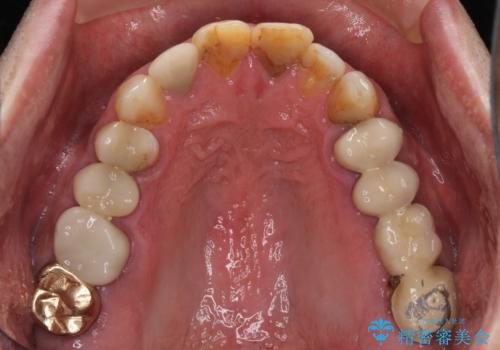

左側は大臼歯2本と小臼歯1本が欠損しているため、インプラント2本を治療したブリッジ、右側は中間欠損であり、前後の歯も加療が必要であったためブリッジによる補綴治療を行うこととしました。

治療後の現在は、より長い期間安定した状態を維持していただくため、就寝時マウスピースを装着するようお願いしております。